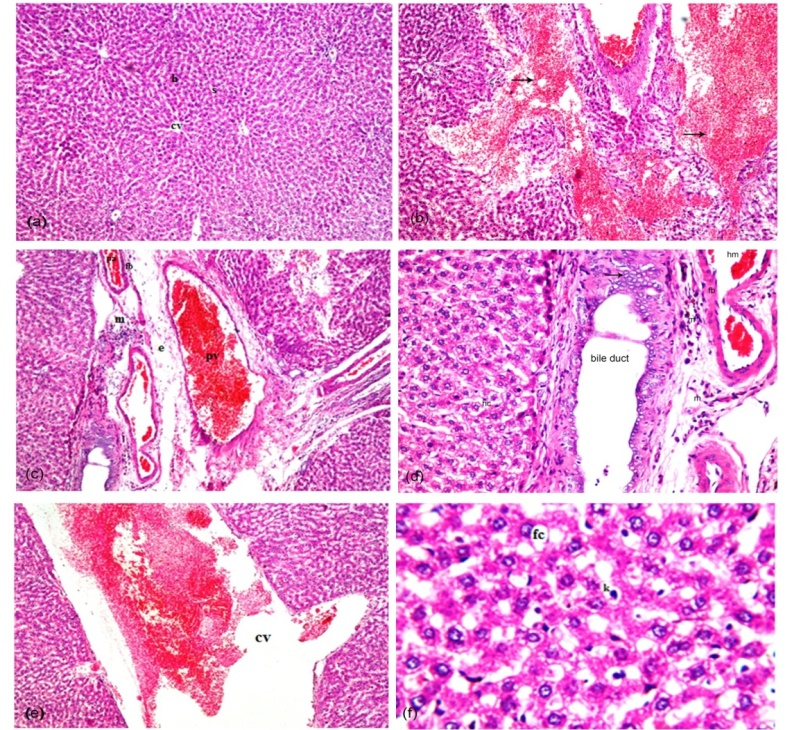

Fig. 6A: Liver paraffin sections stained by haematoxylin and eosin (HandE) for histopathological changes induced by lannate. (a) normal control liver, (b-f) liver treated with lannate. The magnification power was 100x in fig. number (a), (b), (c), and (e) while it was 200x in fig. number (d) and 400x in fig. number (f)

The histological examination of the liver tissue of control rats showed normal hepatic lobules formed of radially arranged cords of hepatocytes (h) extended from the central vein (cv), separated by blood sinusoid (s) as shown in fig. 6Aa. Meanwhile, the microscopic examination of the liver sections of lannate group detected multiple focal haemorrhages in the parenchyma (fig. 6Ab) associated with dilated congested portal vein (pv) as well as edema (e) and focal inflammatory cells infiltration (m) in the portal area with fibrous sheath (fb) around portal artery (fig. 6Ac). In addition, there was hyperplasia in the lining epithelium of the dilated bile duct at the portal area (fig. 6Ad), also fibrous sheath (fb) seen around the wall of portal artery with blood haemorrhage (hm) and inflammatory cells infiltration (m) around portal vein and portal artery as well as hydropic change (hc) in some hepatocytes. Sever dilatation and congestion was detected also in the central vein (fig. 6Ae), in addition to diffuse kupffer cells (k) proliferation was detected in between the degenerated and fatty changed (fc) hepatocytes (fig. 6Af).

On the other hand, normal hepatic architecture detected in the orange juice treated group (fig. 6Bg). While a dilatation in the central vein associated with few inflammatory cells infiltration in the portal area of the post-treatment group (fig. 6Bh). In the pre-treatment group there are few inflammatory cells infiltration was detected surrounding and adjacent the dilated central vein and in the portal area (fig. 6Bi). Also, a diffuse kupffer cells proliferation with few inflammatory cells infiltration were detected in between the hepatocytes (fig. 6Bj) of continuous group.

Fig. 6B: Liver paraffin sections stained by H and E showing ameliorated hepatic architecture in the orange juice treated groups with or without lannate. (g) orange juice treated group, (h) post-treatment group, (i) pre-treatment group, (j) continuous group. The magnification power was 100x in fig. number (h) and (i) while it was 200x in fig. number (g) and (j)